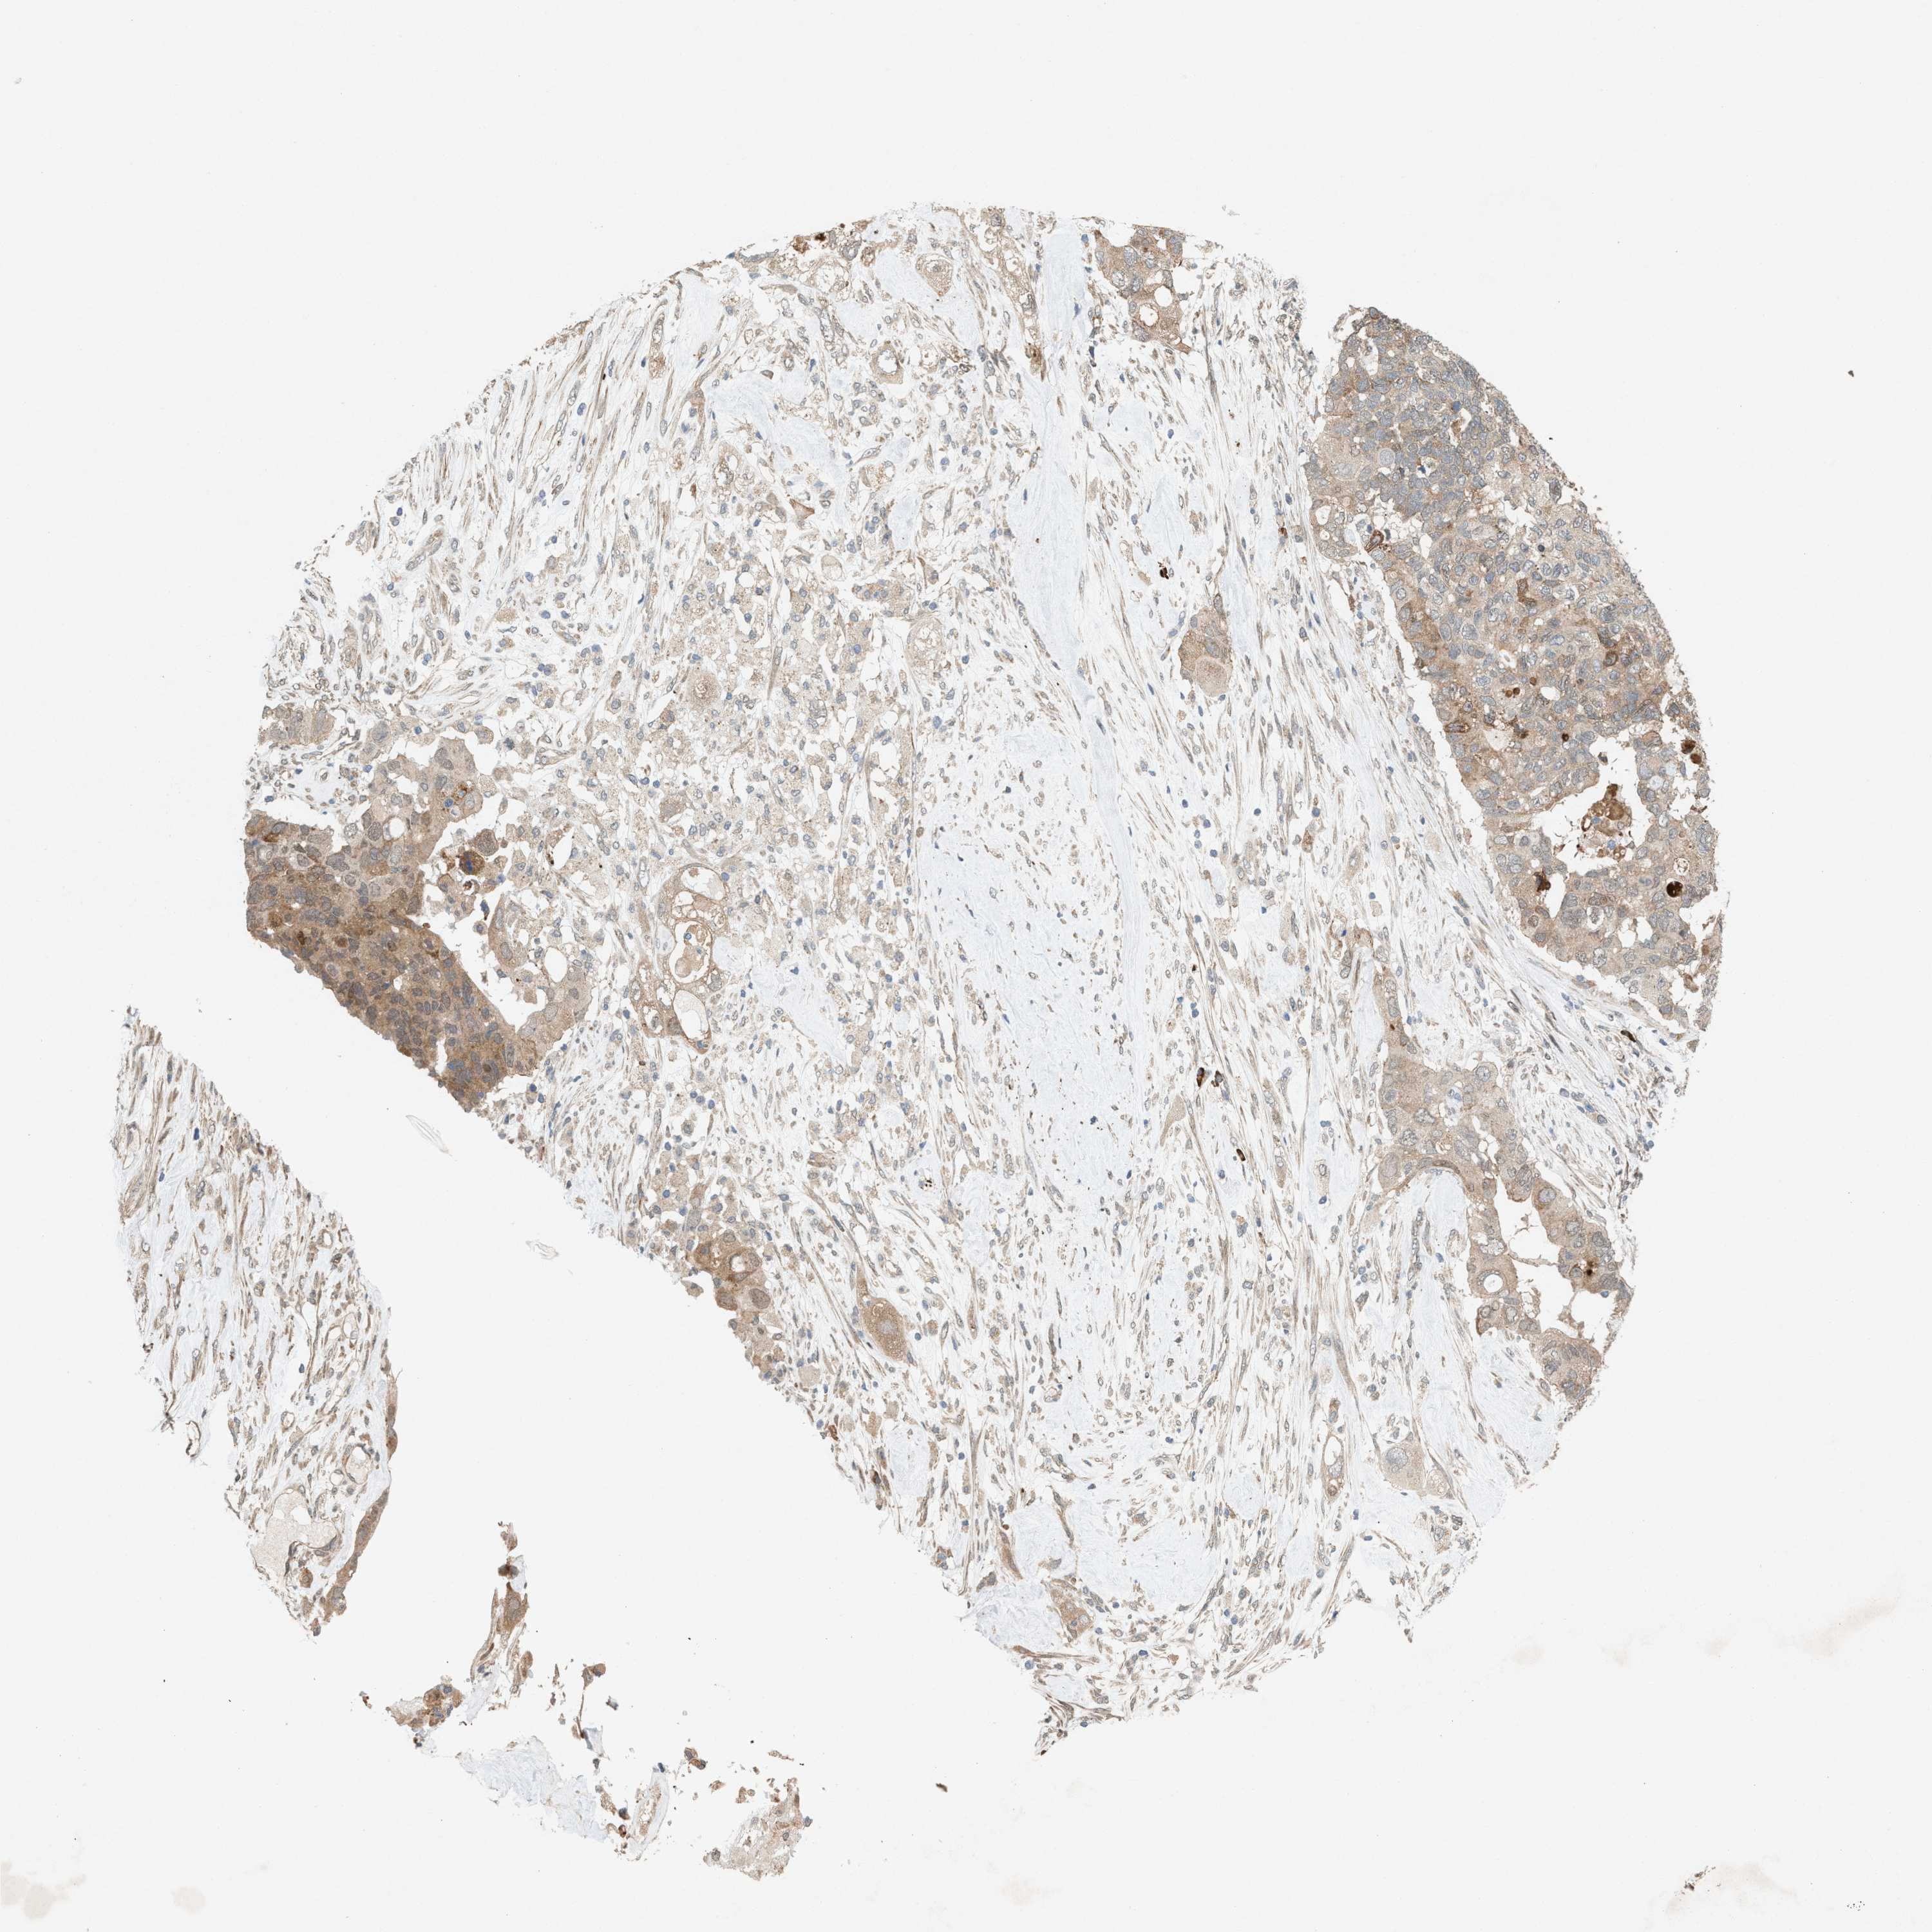

PANCREATIC CANCER - Protein expressioni

A mouse-over function shows sample information and annotation data. Click on an image to view it in a full screen mode. Samples can be filtered based on level of antibody staining by selecting one or several of the following categories: high, medium, low and not detected. The assay and annotation is described here.

Note that samples used for immunohistochemistry by the Human Protein Atlas do not correspond to samples in the TCGA dataset.

Antibody stainingi

Antibody staining in the annotated cell types in the current human tissue is reported as not detected, low, medium, or high, based on conventional immunohistochemistry profiling in selected tissues. This score is based on the combination of the staining intensity and fraction of stained cells.

Each image is clickable and will lead to virtual microscopy that enables deeper exploration of all samples and also displays staining intensity scores, fraction scores and subcellular localization as well as patient and tissue information for each sample.

Antibody HPA022274

Staining

High

Medium

Low

Not detected

Intensity

Strong

Moderate

Weak

Negative

Quantity

>75%

75%-25%

<25%

None

Location

Nuclear

Cytoplasmic/membranous

Cytoplasmic/membranous,nuclear

Adenocarcinoma, NOS